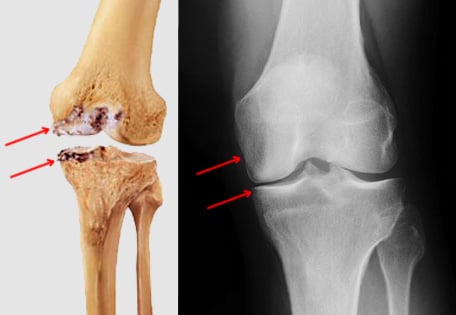

Illustration and X-ray images of medial compartment osteoarthritis of the knee